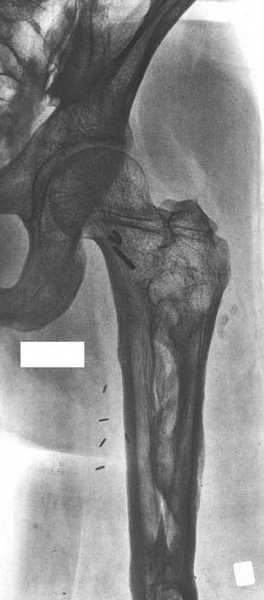

При наличии в института сосудистых хирургов, как альтернативный метод можно было бы предложить графт как показано на снимке.

Не мой случай, но красиво!